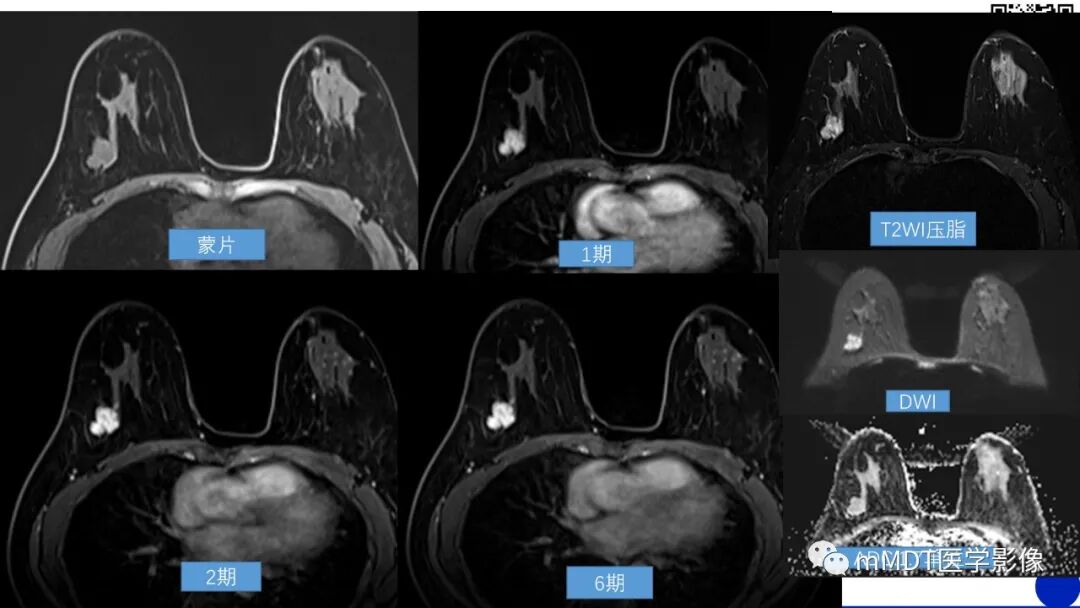

双侧乳腺呈b类,背景实质呈对称性极少强化,右乳外上象限约9点-10点中方向后1/3带距胸壁cm可见一不规则肿块,边缘清晰,T1呈稍低,T2压脂呈稍高,内部强化不均匀,见低信号分隔影,DWI呈高信号,ADC值是1.7,TIC早期快速强化,延迟期呈流入型,考虑良性可能性大,纤维腺瘤?BI-RADS 3类

乳腺腺体呈c类;右乳外上象限后带不规则等密度肿块,大小约--,边界清晰,内见点状钙化影;考虑4A类。MR:右乳外上象限后带距胸壁cm可见一不规则肿块,大小约--,边缘清晰,T1呈稍低信号,T2压脂呈高信号,内见低信号分隔影,DWI呈高信号,ADC值1.7,动态增强早期快速强化,TIC曲线呈流入型,考虑纤维腺瘤,BI-RADS 3类。

早读病例:右侧乳腺外上象限约9点-10点钟方后带可见一不规则肿块,边缘清晰,密度不均,内可见点状钙化,MR:T1呈稍低信号,T2压脂呈高信号,内见低信号分隔影,DWI呈高信号,ADC值1.7,动态增强早期快速强化,TIC曲线呈流入型,腋窝未见肿大淋巴结,虽然形态规整,但是逐渐增大,考虑4A,建议穿刺活检

早读病例:右侧乳腺外上象限约9点-10点钟方后带可见一不规则肿块,边缘清晰,密度不均,内可见点状钙化,MR:T1呈稍低信号,T2压脂呈高信号,内见低信号分隔影,DWI呈高信号(结合ADC值,考虑DWI高信号为T2投射效应所致),ADC值1.7,动态增强早期快速强化,TIC曲线呈流入型,腋窝未见肿大淋巴结。形态学上多发分叶,边缘不光整,但无毛刺,界限清晰,dwi和血液动力学倾向于良性病变。临床表现为病变逐渐增大,综合分析推测是低度恶性肿瘤,考虑4A,建议穿刺活检

双侧乳腺呈c类,BPE呈对称少许强化,右乳外上象限约9-10点钟方向,后1/3带,距胸壁约cm可见一不规则肿块,边缘清晰,蒙片与腺体呈等信号,内部强化较均匀,似见低信号分隔影,DWI呈高信号,ADC值是1.7,TIC呈快速流入型,增强和弥散都不得分,形态学不好把握,结合年龄和病史考虑BI-RADS 4A类

MRI双乳纤维腺体组织B类,实质背景强化极少,右乳外上象限肿块样强化,DWI成高信号,ADC减低不明显,TIC成快速流入型曲线,双侧腋窝未见肿大淋巴结,考虑BI-RADS 4A类,结核穿刺活检综合分析。

MRI双乳纤维腺体组织B类,实质背景强化极少,右乳外上象限肿块影,T1WI呈低信号,T2WI呈稍高信号, DWI呈高信号,ADC减低不明显( >1.35×10﹣³㎜²/s) 。增强后呈不规则肿块样强化,内见不强化分隔,边缘比较光滑。TIC呈流入型曲线,双侧腋窝未见肿大淋巴结,积0分,考虑BI-RADS 3类,纤维腺瘤?建议结合临床

徐志 06:52

实质背景强化极少,右乳外上象限分叶肿块影,T1WI呈低信号,T2WI呈稍高信号, DWI呈高信号,ADC减低不明显( 1.7×10﹣³㎜²/s) 。增强后呈不规则肿块样强化,内见不强化分隔,边缘比较光滑。TIC呈流入型曲线,双侧腋窝未见肿大淋巴结,考虑BI-RADS 3类,纤维腺瘤可能。

中年女性,肿块渐进性增大,分叶状,边界清,内有散在钙化及小囊变,纤维分隔,弥散有受限,流入型曲线,考虑BI-RADS 4a,建议穿刺。叶状肿瘤,纤维腺瘤可能性大

双侧乳腺腺体类型为ACR C 型,背景实质呈对称性极少强化,右乳外上象限约10点钟方向位于乳房后1/3带可见一不规则肿块,可见分叶,边缘清晰,T1呈稍低信号,T2压脂呈高信号,肿块强化不均匀,内见低信号分隔不强化,DWI呈高信号,ADC值是1.7,TIC早期快速强化,延迟期呈流入型曲线,考虑良性,纤维腺瘤可能性大 BI-RADS 3类

双侧乳腺腺体类型为ACR C 型,质背景强化极少,右乳外上象限分叶肿块影,T1WI呈低信号,T2WI压脂呈稍高信号, DWI呈高信号,ADC减低不明显( 1.7×10﹣³㎜²/s) 。增强后呈不规则肿块样强化,内见不强化分隔,边缘比较光滑。快速强化, TIC呈流入型曲线,双侧腋窝未见肿大淋巴结,考虑BI-RADS 3类,纤维腺瘤可能。

MRT1等信号,T2高信号,背景实质呈极少强化,肿块呈明显强化,内见低信号分隔,ADC值1.7(>1.35),增强早期呈快速强化,延迟期呈流入型。

其三,磁共振,形态学,不规则形或椭圆形肿块,边缘清晰,血流动力学:增强早期快速强化,延迟期渐增型,功能成像:ADC不低,三方面都支持良性,所以这个病灶可以归到3类,如果不放心4A类也没问题,如果结合临床查体可能更准确